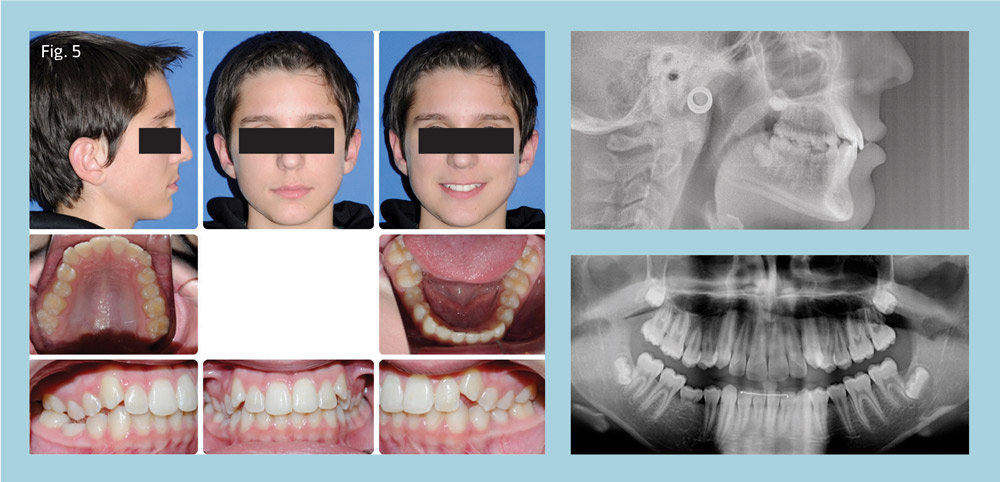

The patient, a healthy 13-year-old, presented with congenitally missing tooth 29, ankylosed tooth T, Class II, Division 2 malocclusion, 50 percent overbite, 2.5mm overjet, mild upper and lower crowding, slightly convex facial profile, and good facial balance (Fig. 5).